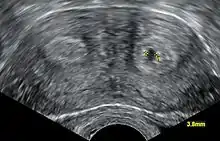

يَتم استخدام الموجات فوق الصَوتية في إظهار صورة مقطعية للرحم ثنائي القرنين،[1] حيثُ يَظهر الرَحم مع اثنين من التجاويف وكأنها قُرون على التَوالي، ويُمكن كذلك استخدام التصوير بالرنين المغناطيسي في حالة الرَحم ذو القرنين،[2] ولكن نادرًا ما يتم الكشف عن الرَحم ثنائي القرنين، حيثُ لا يوجد أعراض لَه، ولا يُؤثر على الولادة أو الحَمل، ولكن عادةً ما يَتم الكَشف عنه أثناء إجراء العمليات القيصيرة ويكون ذلك بسبب سوء الوُلاد والصعوبة فيه، وَفي الكثير من حالات العقم يَتم الكَشف عن الرحم ذو القرنين.